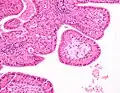

The appearance of this tumor under the microscope is unique. There are cystic spaces surrounded by two uniform rows of oncocytes, which are epithelial cells with abundant, granular, eosinophilic cytoplasm.[7] The cystic spaces have epithelium referred to as papillary infoldings that protrude into them. Additionally, the epithelium has lymphoid stroma with germinal center formation.

Low magnification micrograph of a Warthin tumor arising from the parotid gland.

Intermediate magnification micrograph of a Warthin tumor.